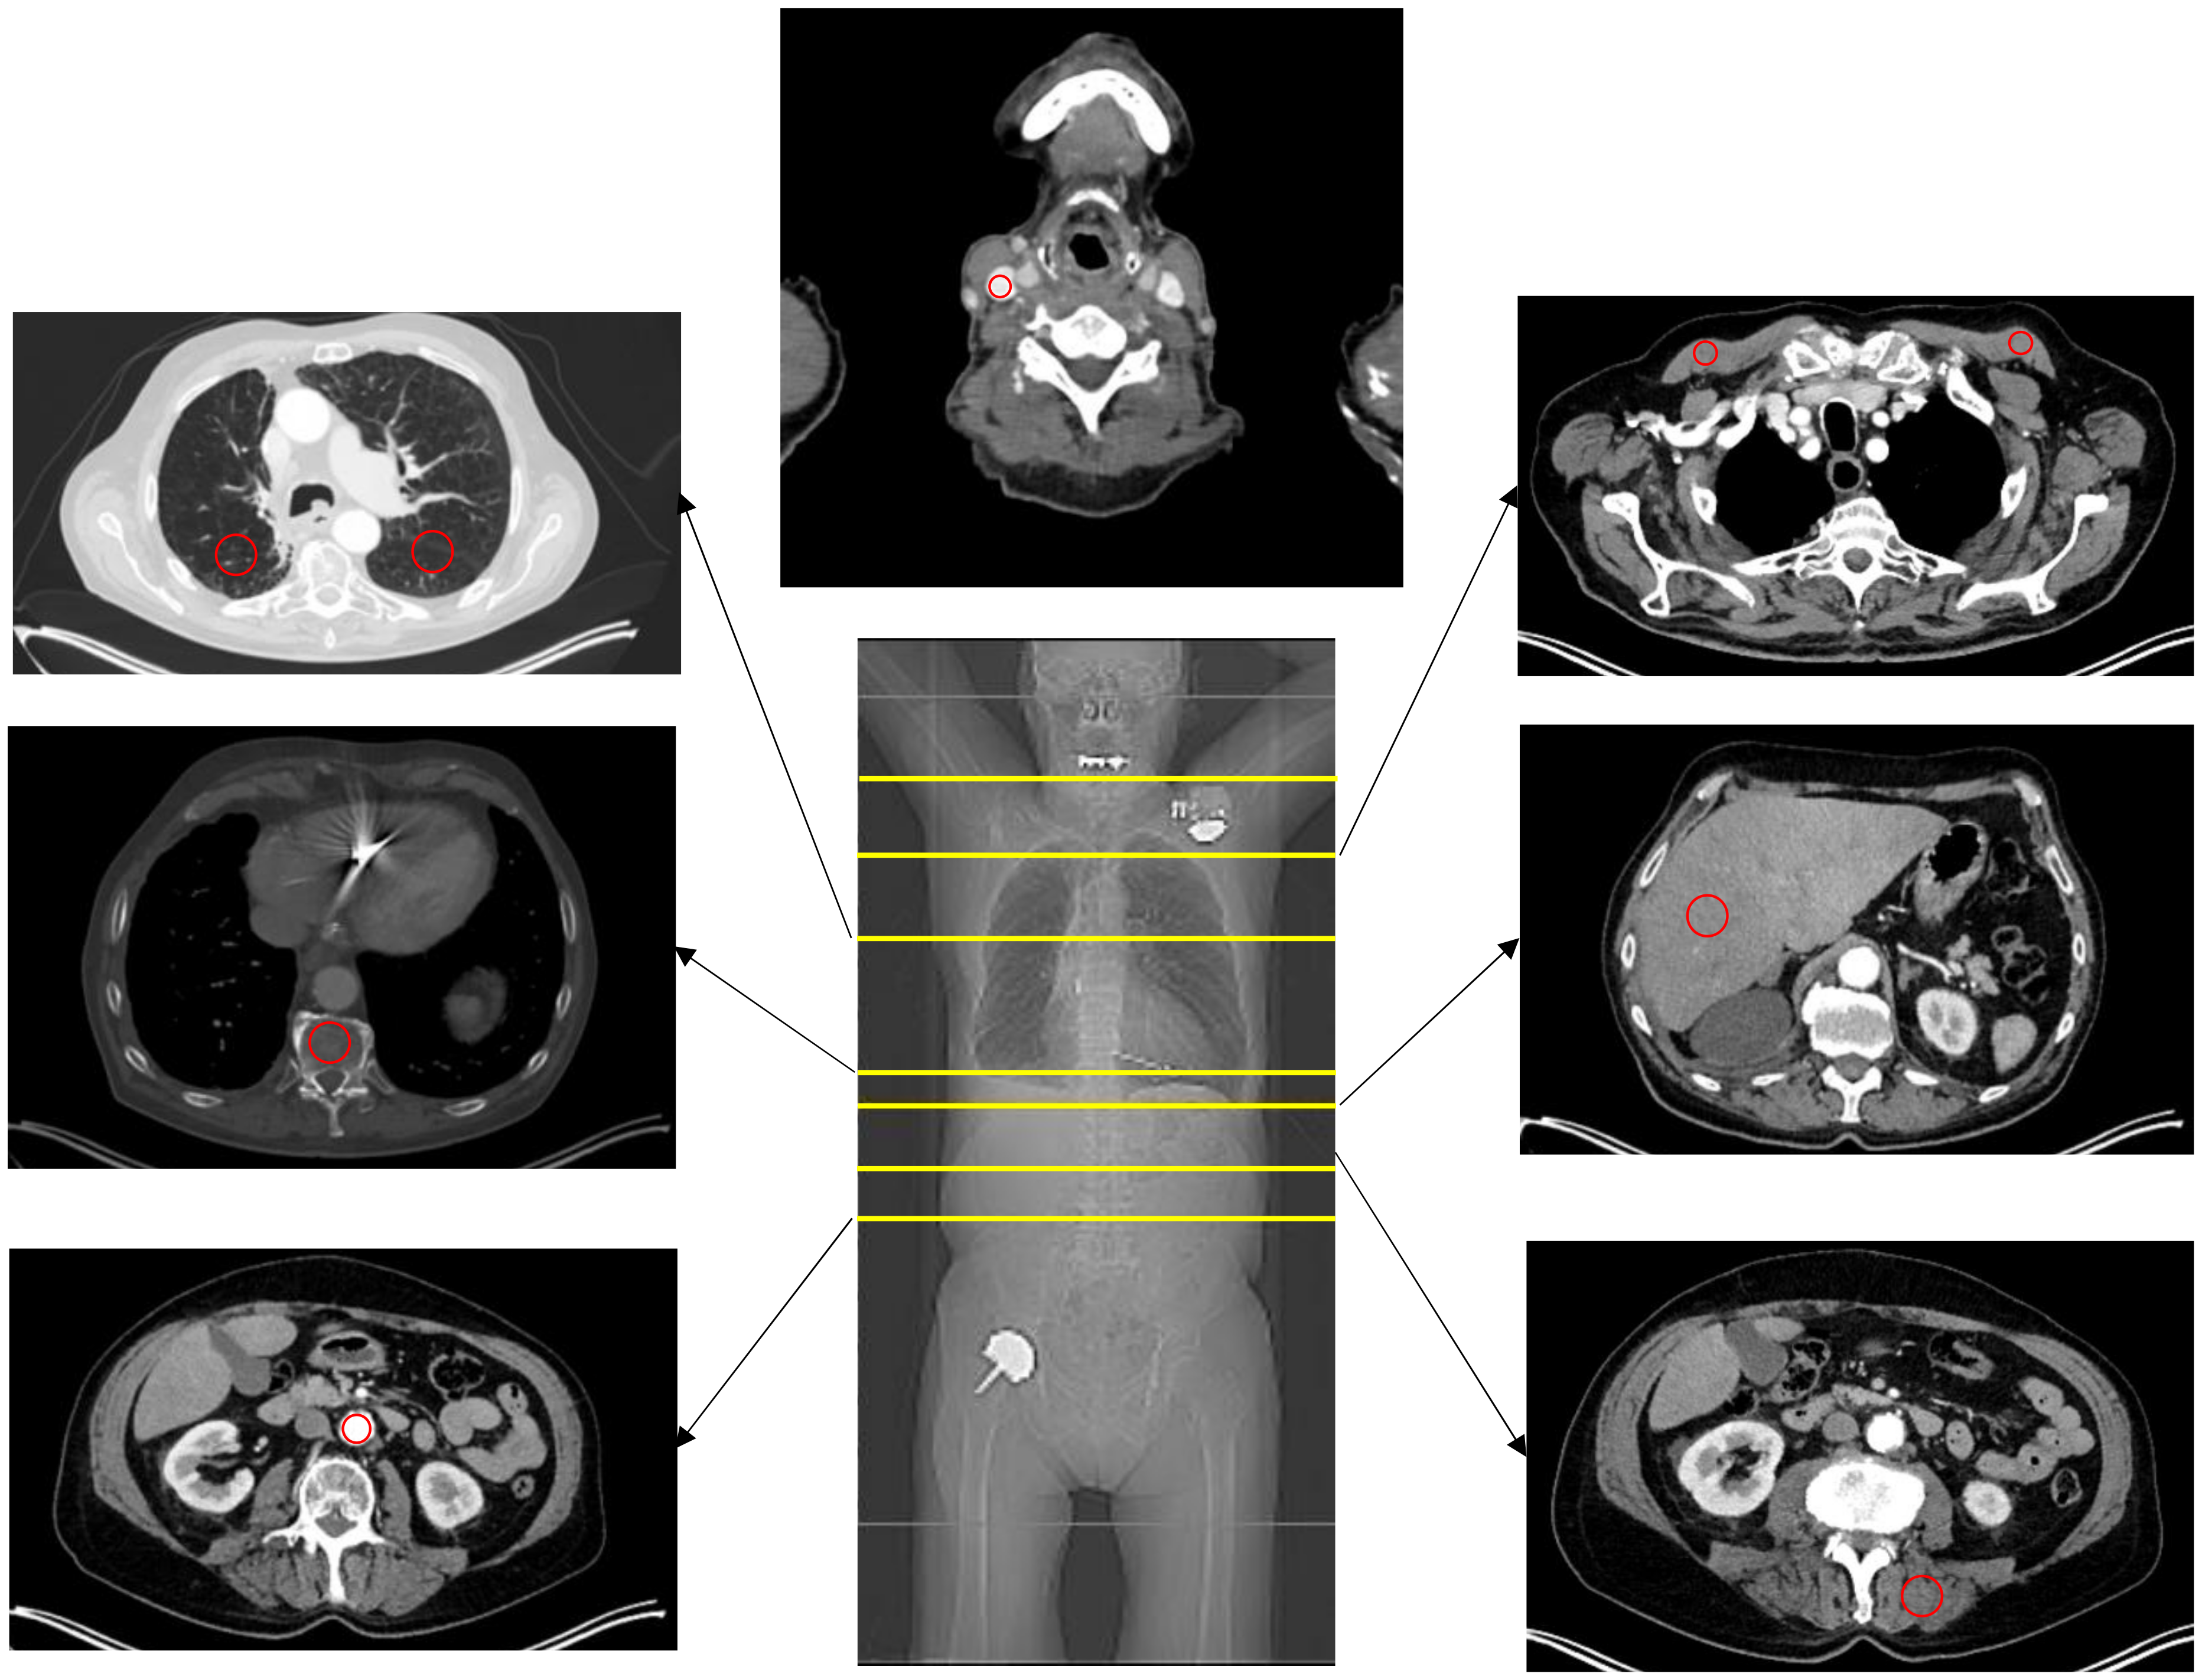

2.5. Image Analysis

3.2. HU Measurements

3.3. SUV Measurements